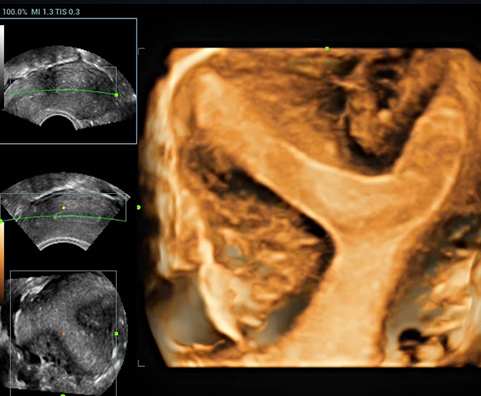

Sejak didirikan, Mindray terus mencari cara baru untuk meningkatkan keandalan diagnostik. Didukung Teknologi ZONE Sonography? terkini, platform ZST+ baru Resona 7 meningkatkan kualitas gambar ultrasound melalui pengambilan zona dan pemrosesan data saluran.

Selain kualitas gambar premium, Resona 7 juga meningkatkan kemampuan penelitian klinis dengan V Flow revolusioner untuk evaluasi hemodinamika vaskular, serta pengambilan penampang tercanggih dari rangkaian data 3D untuk diagnosis CNS pada janin. Kombinasi pengoperasian multisentuh berbasis gerakan yang paling intuitif dengan semua fitur klinis penting membuat Resona 7 menjadi gebrakan baru dalam inovasi ultrasound.